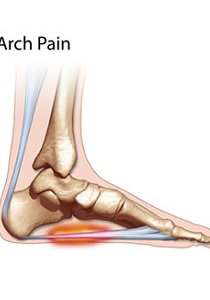

Arch Pain

The term arch pain (often referred to as arch strain) refers to an inflammation and/or burning sensation at the arch of the foot.

There are many different factors that can cause arch pain. A structural imbalance or an injury to the foot can often be the direct cause. However, most frequently the cause is a common condition called plantar fasciitis. The plantar fascia is a broad band of fibrous tissue located along the bottom surface of the foot that runs from the heel to the forefoot. Excessive stretching of the plantar fascia, usually due to over-pronation (flat feet), causes plantar fasciitis. The inflammation caused by the plantar fascia being stretched away from the heel often leads to pain in the heel and arch areas. The pain is often extreme in the morning when an individual first gets out of bed or after a prolonged period of rest. If this condition is left untreated and strain on the longitudinal arch continues, a bony protrusion may develop, known as a heel spur. It is important to treat the condition promptly before it worsens.

This is a common foot condition that can be easily treated. If you suffer from arch pain avoid high-heeled shoes whenever possible. Try to choose footwear with a reasonable heel, soft leather uppers, shock absorbing soles and removable foot insoles. When the arch pain is pronation related (flat feet), an orthotic designed with a medial heel post and proper arch support is recommended for treating the pain. This type of orthotic will control over-pronation, support the arch and provide the necessary relief.